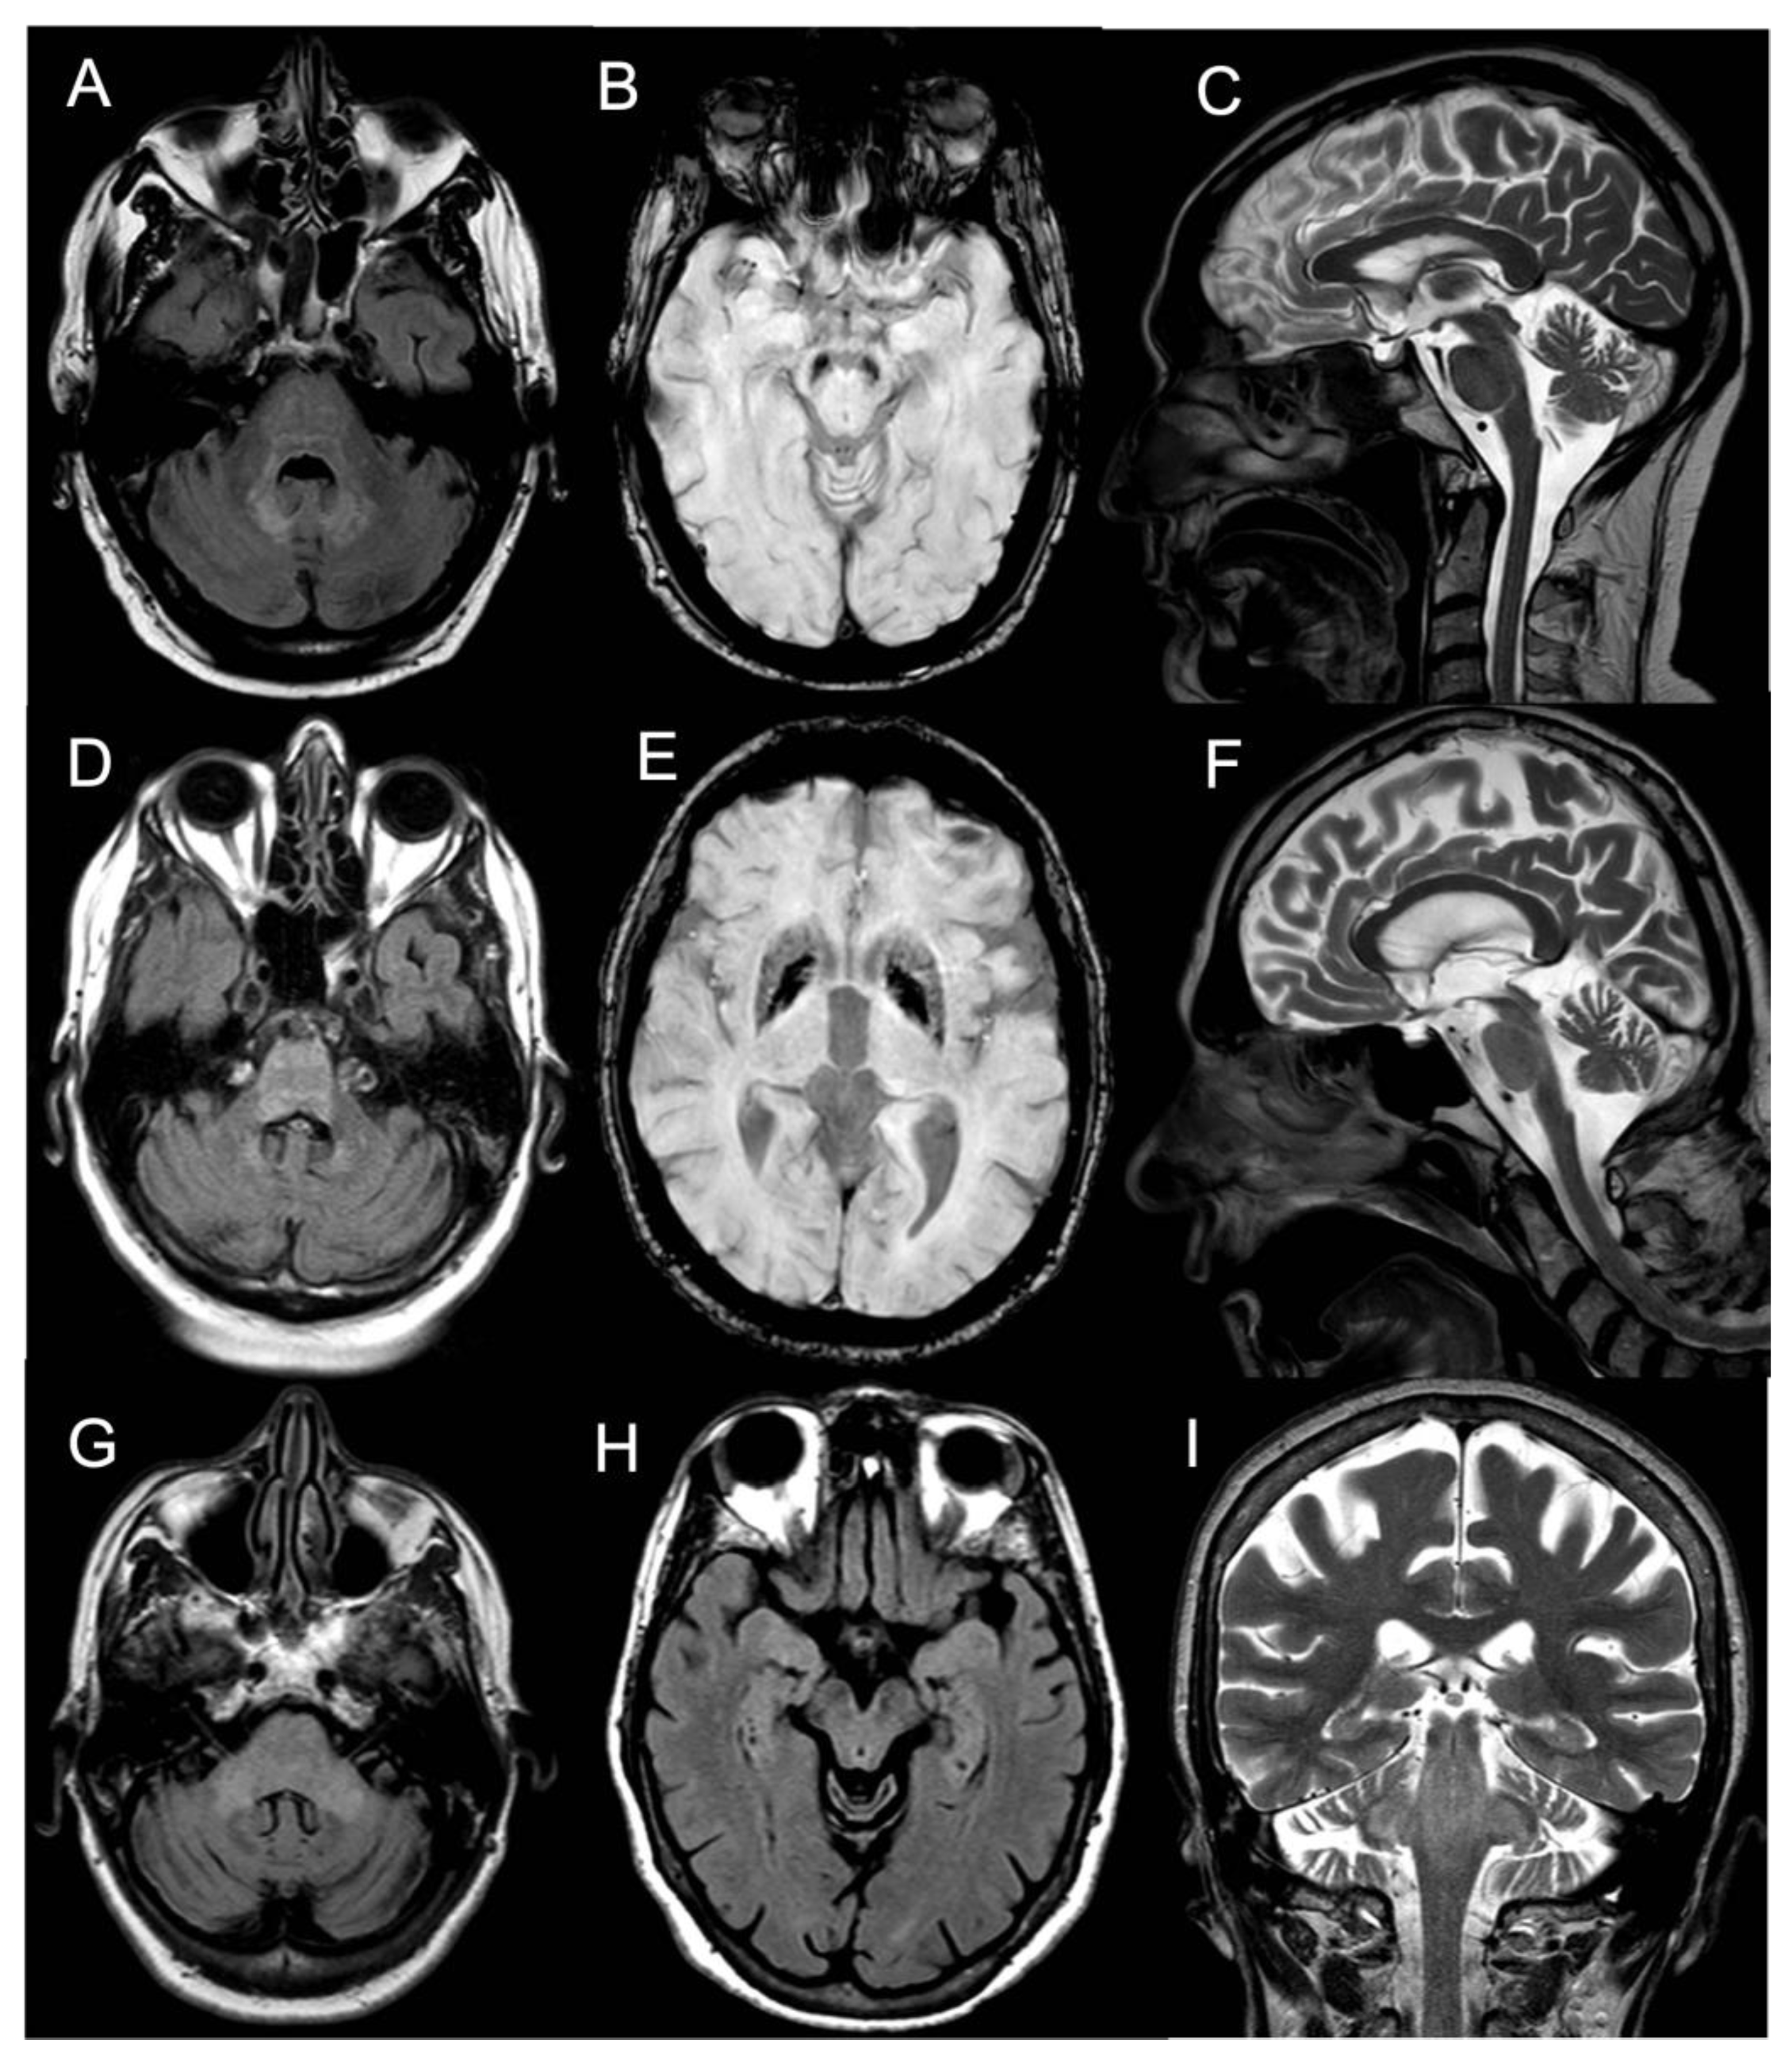

Brain MRI showed T2/FLAIR hyperintense signal alterations without contrast enhancement variably involving the white matter of cerebellar hemispheres, middle cerebellar peduncles, dentate nuclei, pons, and midbrain and cerebral peduncles in all cases (Figure 1). Three patients (Pts 1, 2, 4) also presented similar supratentorial T2/FLAIR hyperintensities variably involving the paratrigonal area, posterior arm of the internal capsule, globus pallidus, peri-aqueductal, and parahippocampal areas, with evidence of gadolinium contrast enhancement in the paratrigonal area not shown in Pt 3. Moreover, signs of cerebellar atrophy and bilateral hypointense signal abnormalities in basal ganglia on SWI sequences, suggestive of iron deposition, were evident in Pts 1, 3, and 4 (Figure 1). Of note, in Pt 2 manifesting a subacute neurological outcome, MRI also showed two nodular lesions (30 × 20 × 20 mm3) in the right cerebellar hemisphere with contrast enhancement (Figure 2) and elevated levels of r-CBV (regional cerebral blood volume) on the perfusion study and DWI-restriction, indicative of hypercellularity. Finally, Pt 3, affected by diabetes insipidus, also presented an empty sella. Signs of paranasal sinuses or mastoid inflammation were evident in three patients (Pts 1, 2, and 3). Spinal cord MRI was normal in all patients.

Figure 1. Panel showing brain MRI of Pt #1 (AC), Pt #3 (DF), and Pt #4 (GI). (A) Transverse FLAIR scan (pons level) of Pt #1 showing mild hyperintensity of the pons, both MCPs, dentate nuclei. (B) Transverse SWAN scan (mesencephalon level) of Pt #1 showing marked hypointense signal (metal deposits) of bilateral substantia nigra. (C) Sagittal T2-weighted scan of Pt #1 showing slight vermian cerebellar atrophy. (D) Transverse FLAIR scan (pons level) of Pt #3 showing hyperintensity of the pons and dentate nuclei. (E) Transverse SWAN scan (thalami level) of Pt #3 showing marked hypointense signal (metal deposits) of putamina and globi pallidi. (F) Sagittal T2-weighted scan of Pt #3 showing vermian cerebellar atrophy. (G) Transverse FLAIR scan (pons level) of Pt #4 showing hyperintensity of the pons and both MCPs. (H) Transverse FLAIR scan (mesencephalon level) of Pt #4 showing hyperintensity of the mesencephalon and parahippocampal cortices. (I) Coronal T2-weighted scan of Pt #4 showing hyperintensity of the pons, both SCPs and MCPs. Abbreviations: Flair: fluid-attenuated inversion recovery; MCP: middle cerebellar peduncle; SWAN: susceptibility-weighted angiography; SCP: superior cerebellar peduncle.

Brainsci 13 00026 g001